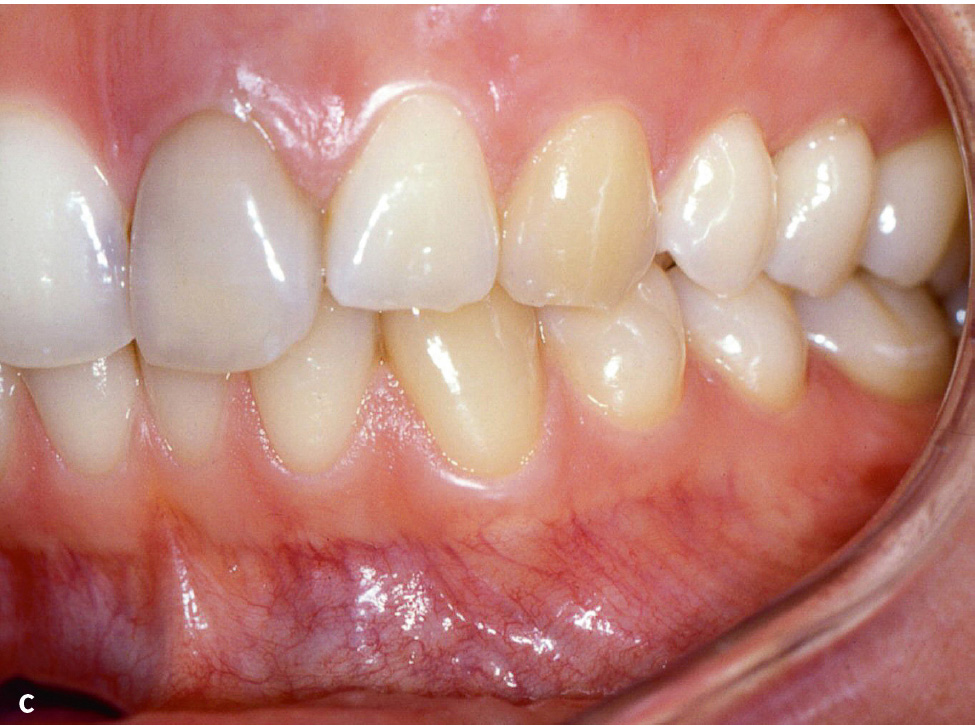

Abb. 4a bis c Patientin im Alter von 24 Jahren mit generalisierter aggressiver Parodontitis18, Parodontitisstadium III (Molaren-Inzisiven-Muster) Grad C. a) Röntgenstatus: Knochenabbau bis ins apikale Wurzeldrittel an den Zähnen 16, 21 und 26 (Stadium III), im Unterkiefer geringerer Knochenabbau bis 50 % der Wurzellänge an Zahn 44, kein Zahnverlust, aber Sondierungstiefen ≥ 6 mm an Zahn 16, Grad-III-Furkationsbeteiligung an Zahn 16 und 26, distal Zahn 16 Knochenabbau 70 % der Wurzellänge (geteilt durch das Lebensalter = 2,9; Grad C). b und c) Klinische Ansicht: keine supragingivale Plaque, Destruktion überschreitet Erwartungen durch Biofilmauflagerungen (Grad C).

In der ICD-10 kommt Parodontitis noch als Chronische Parodontitis (K05.3) vor. Dazu werden gruppiert: Chronische Perikoronitis, Parodontitis complex, -simplex und -o. n. A. (ohne nähere Angaben). Ferner wird die Diagnose Parodontose (K05.4) aufgelistet. Ausdrücklich wird die „juvenile Parodontose“ eingeschlossen3. Als juvenile Parodontitis wurde ein Großteil der klinischen Bilder vor 1999 bezeichnet, die danach aggressive Parodontitis genannt wurden7. Parodontitis, die bereits bei Kindern und Jugendlichen auftritt, bei der die Zerstörung im Vergleich zum Lebensalter sehr fortgeschritten ist oder mehr Zerstörung festzustellen ist, als der vorhandene Biofilm erklären kann (Abb. 4), werden in der neuen Klassifikation mit einem Grad C gekennzeichnet (hohe Progressionsrate)9,10. Wie kann es sein, dass die ICD-10 für die infektiös-entzündliche Zerstörung des Parodonts eine Wortendung verwendet, die allgemein für degenerative Prozesse verwendet wird (-ose)? In vielen Fällen der Parodontitis mit hoher Progressionsrate besteht ein Missverhältnis zwischen der Menge der bakteriellen Ablagerungen sowie der klinisch sichtbaren Entzündung (Schwellung, Rötung) und dem Ausmaß der Gewebedestruktion. Dies führte dazu, dass der Begriff „Periodontosis/Parodontosis“ zum Teil synonym wie juvenile Parodontitis verwendet wurde11. Darüber hinaus gibt es noch Sonstige Krankheiten des Parodonts (K05.5) und Krankheit des Parodonts, nicht näher bezeichnet (K05.6)3.